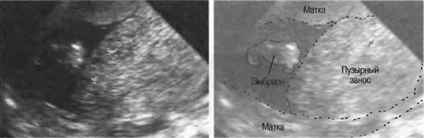

Пузырчатый занос, или молярная беременность, представляет собой аномалию, при которой в матке формируется не нормальный эмбрион, а скопление пузырьков, заполненных жидкостью. Это состояние возникает в результате нарушения процесса оплодотворения и последующего развития плода. В норме после оплодотворения яйцеклетка начинает делиться и развиваться, но при пузырчатом заносе происходит аномалия, в результате которой вместо нормального плода образуются пузырьки, представляющие собой атипичные ткани.

Существует два основных типа пузырчатого заноса: полная и частичная молярная беременность. При полной форме отсутствует нормальная эмбриональная ткань, и все ткани, которые развиваются, представляют собой аномальные пузырьки. Частичная форма подразумевает наличие как аномальных, так и нормальных тканей, но в этом случае также не формируется жизнеспособный плод.

Эксперты в области акушерства и гинекологии подчеркивают, что пузырчатый занос является серьезным осложнением беременности, требующим внимательного подхода к диагностике и лечению. Основные признаки заболевания включают аномально высокий уровень ХГЧ, отсутствие сердцебиения плода и характерные изменения на УЗИ, такие как наличие пузырьков в матке. Для точной диагностики врачи рекомендуют проводить комплексное обследование, включая ультразвуковое исследование и анализы крови. Важно отметить, что ранняя диагностика позволяет избежать серьезных осложнений и выбрать оптимальную тактику лечения, что особенно актуально для сохранения здоровья женщины и ее будущих беременностей.

Диагностика с помощью УЗИ: Одним из основных методов диагностики пузырчатого заноса является ультразвуковое исследование. На УЗИ можно увидеть характерные «пузырьки» в матке, которые представляют собой скопления аномальных тканей. Это позволяет врачам быстро и точно определить наличие заболевания.

Чтобы увидеть, как выглядит пузырчатый занос, можно посмотреть фото в интернете. Обычно на ультразвуковом исследовании четко видны пузыри, которые располагаются внутри матки. Как можно понять, при таких изменениях в органе, развитие здорового плода не может происходить.